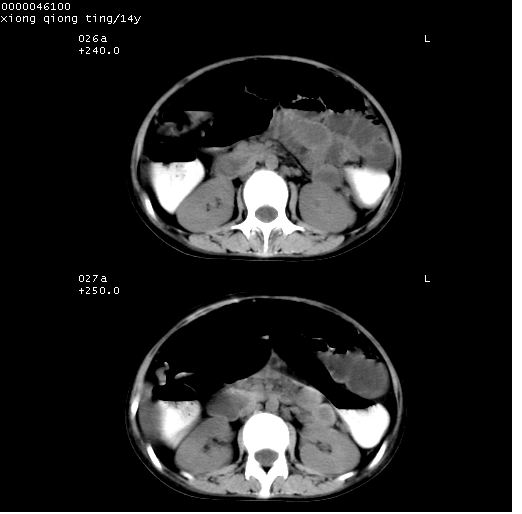

中下腹及盆腔ct轴位平扫+增强扫描(层厚10mm,螺距1.0,重建间隔10mm),图像如下:

(注:患儿检查当日上午9时口服胃肠道对比剂,下午3时许行ct扫描检查,未行对比剂直肠保留灌肠,检查当日患儿腹泻)

中下腹及盆腔ct轴位扫描(ps+ce)提示:腹部肠管明显充气扩张,并见数个不同宽度之气液平面;疑不全性肠梗阻或肠郁张。临床会诊考虑为患儿腹泻,肠郁张所致;后来未经特殊处理,患儿大便恢复正常,亦无腹胀。

临床出院诊断:1)结核性腹膜炎。2)腹膜后淋巴结结核。3)脂肪肝。